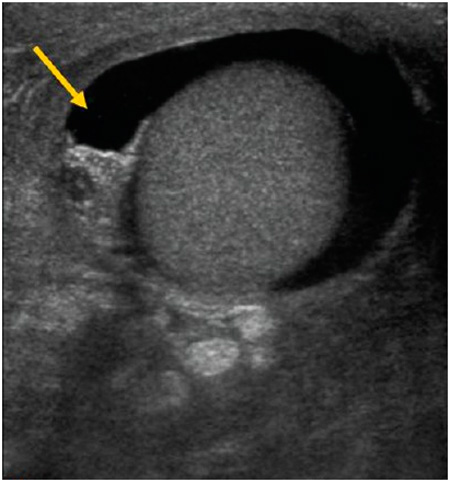

Ellentétben a hydrocele, a diaphanoscope haematocele nem jelenik meg a vörös fény. Haematocele is más ultrahang jeleket.

Ábra. Ultrahangos képalkotó hydrocele.

Ábra. Ultrahangos képalkotó haematocele. Testis körül egy folyadék, de a szerkezete nem homogén, az üreget osztva több partíciót.